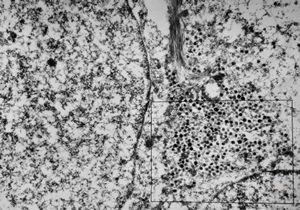

F, 7y. | molluscum contagiosum … virions

F, 7y. | molluscum contagiosum … virions